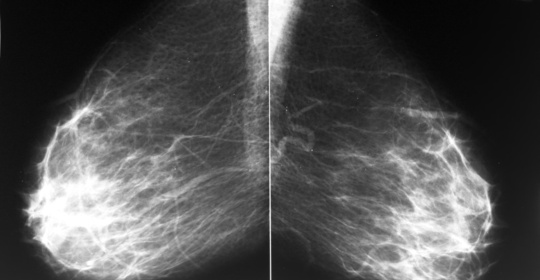

乳房腫塊:識別與防治

停經後乳房腫塊:原因與處理

乳房腫塊:原因及治療措施

乳房腫塊:典型症徵與診斷方法

乳房腫塊:纖維囊腫、胸部水泡痛與纖維囊腫變大

乳房腫塊:症狀、原因及診斷